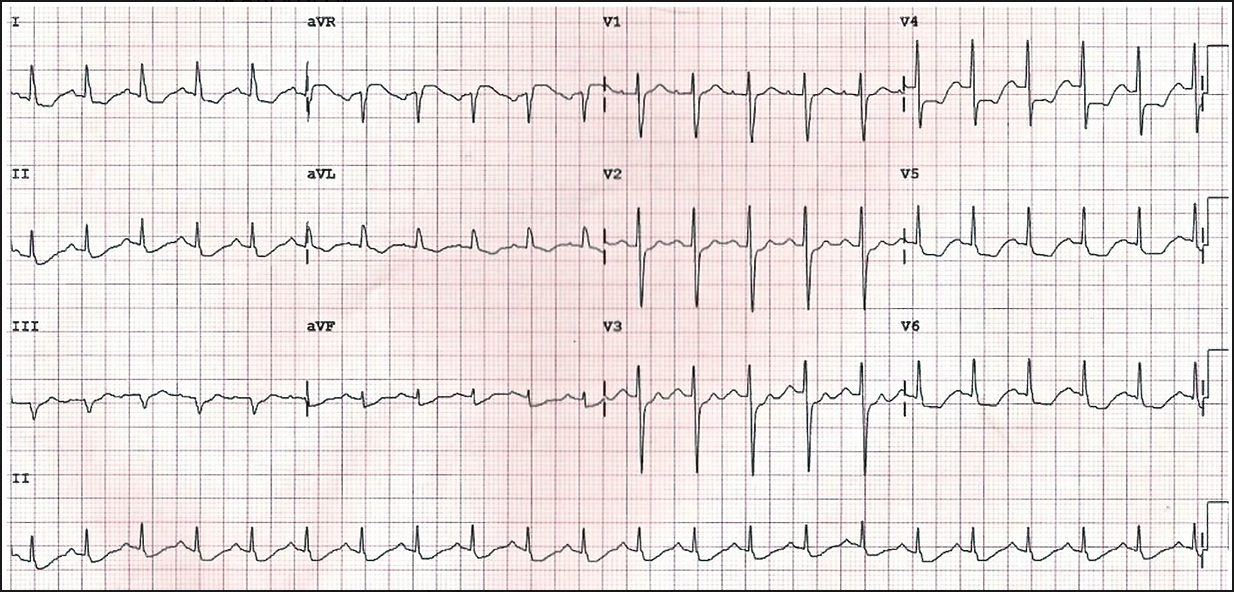

Anterior MI:

This happens due to occlusion of the left anterior descending coronary artery

Look at the chest leads V1-6. There is elevation in the ST segment for each of these.

This suggests that the MI has occurred in the anterolateral segment of the heart since the anterior leads V3 and 4 as well as the lateral leads V5 and 6 have the most marked elevation.

NOTE: there is also reciprocal ST depression in the inferior leads, mainly III and aVF